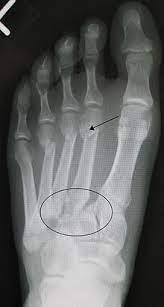

Radiologists must have a thorough understanding of anatomy, mechanisms, and patterns of these injuries to diagnose and help.

Radiologists must have a thorough understanding of anatomy, mechanisms, and patterns of these injuries to diagnose and help. A lisfranc injury, also known as a lisfranc fracture, happens when bones break or ligaments tear in the region in the middle of the feet. A lisfranc injury occurs when one or more of the metatarsal bones are displaced from the tarsus, which is a cluster of bones at the top of the foot, just below the ankle joint. However, most athletes are able to successfully. Stable lisfranc injuries that do not require surgery may cause an athlete to miss 2 months or more of their season. Lisfranc injuries are a spectrum of injuries to the tarsometatarsal joint complex of the midfoot. Lisfranc injury or midfoot injury that result if bones in the midfoot are broken or ligaments that support the midfoot are torn. • medial edge of 2nd mt base should line up with the medial edge of middle cuneiform. A lisfranc injury or lisfranc sprain is an injury to the ligaments in the middle part of the foot, called the midfoot. Lisfranc injury indicates disruption between. Recovery can be slow and painful. It can occur in one or both feet. Ebraheim's animated educational video describing lisfranc injury.